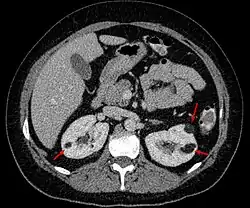

| Angiomyolipoma in both kidneys (arrows) in computer tomography. The tumours are hypodense (dark) due to fat content. | |

Three methods of scanning can detect angiomyolipomas: ultrasound, computed tomography (CT), and magnetic resonance imaging (MRI).[5] Ultrasound is standard and is particularly sensitive to the fat in angiomyolipomas, but less so to the solid components. However, accurate measurements are hard to make with ultrasound, particularly if the angiomyolipoma is near the surface of the kidney (grade III).[4] CT is very detailed and fast, and allows accurate measurement. However, it exposes the patient to radiation and the dangers that a contrast dye used to aid the scanning may itself harm the kidneys. MRI is safer than CT, but many patients (particularly those with the learning difficulties or behavioural problems found in tuberous sclerosis) require sedation or general anaesthesia, and the scan cannot be performed quickly.[3] Some other kidney tumours contain fat, so the presence of fat is not diagnostic. Distinguishing a fat-poor angiomyolipoma from a renal cell carcinoma (RCC) can be difficult.[6] Both minimal fat AMLs and 80% of the clear-cell type of RCCs display signal drop on an out-of-phase MRI sequence compared to in-phase.[7] Thus, a lesion growing at greater than 5 mm per year may warrant a biopsy for diagnosis.[3]